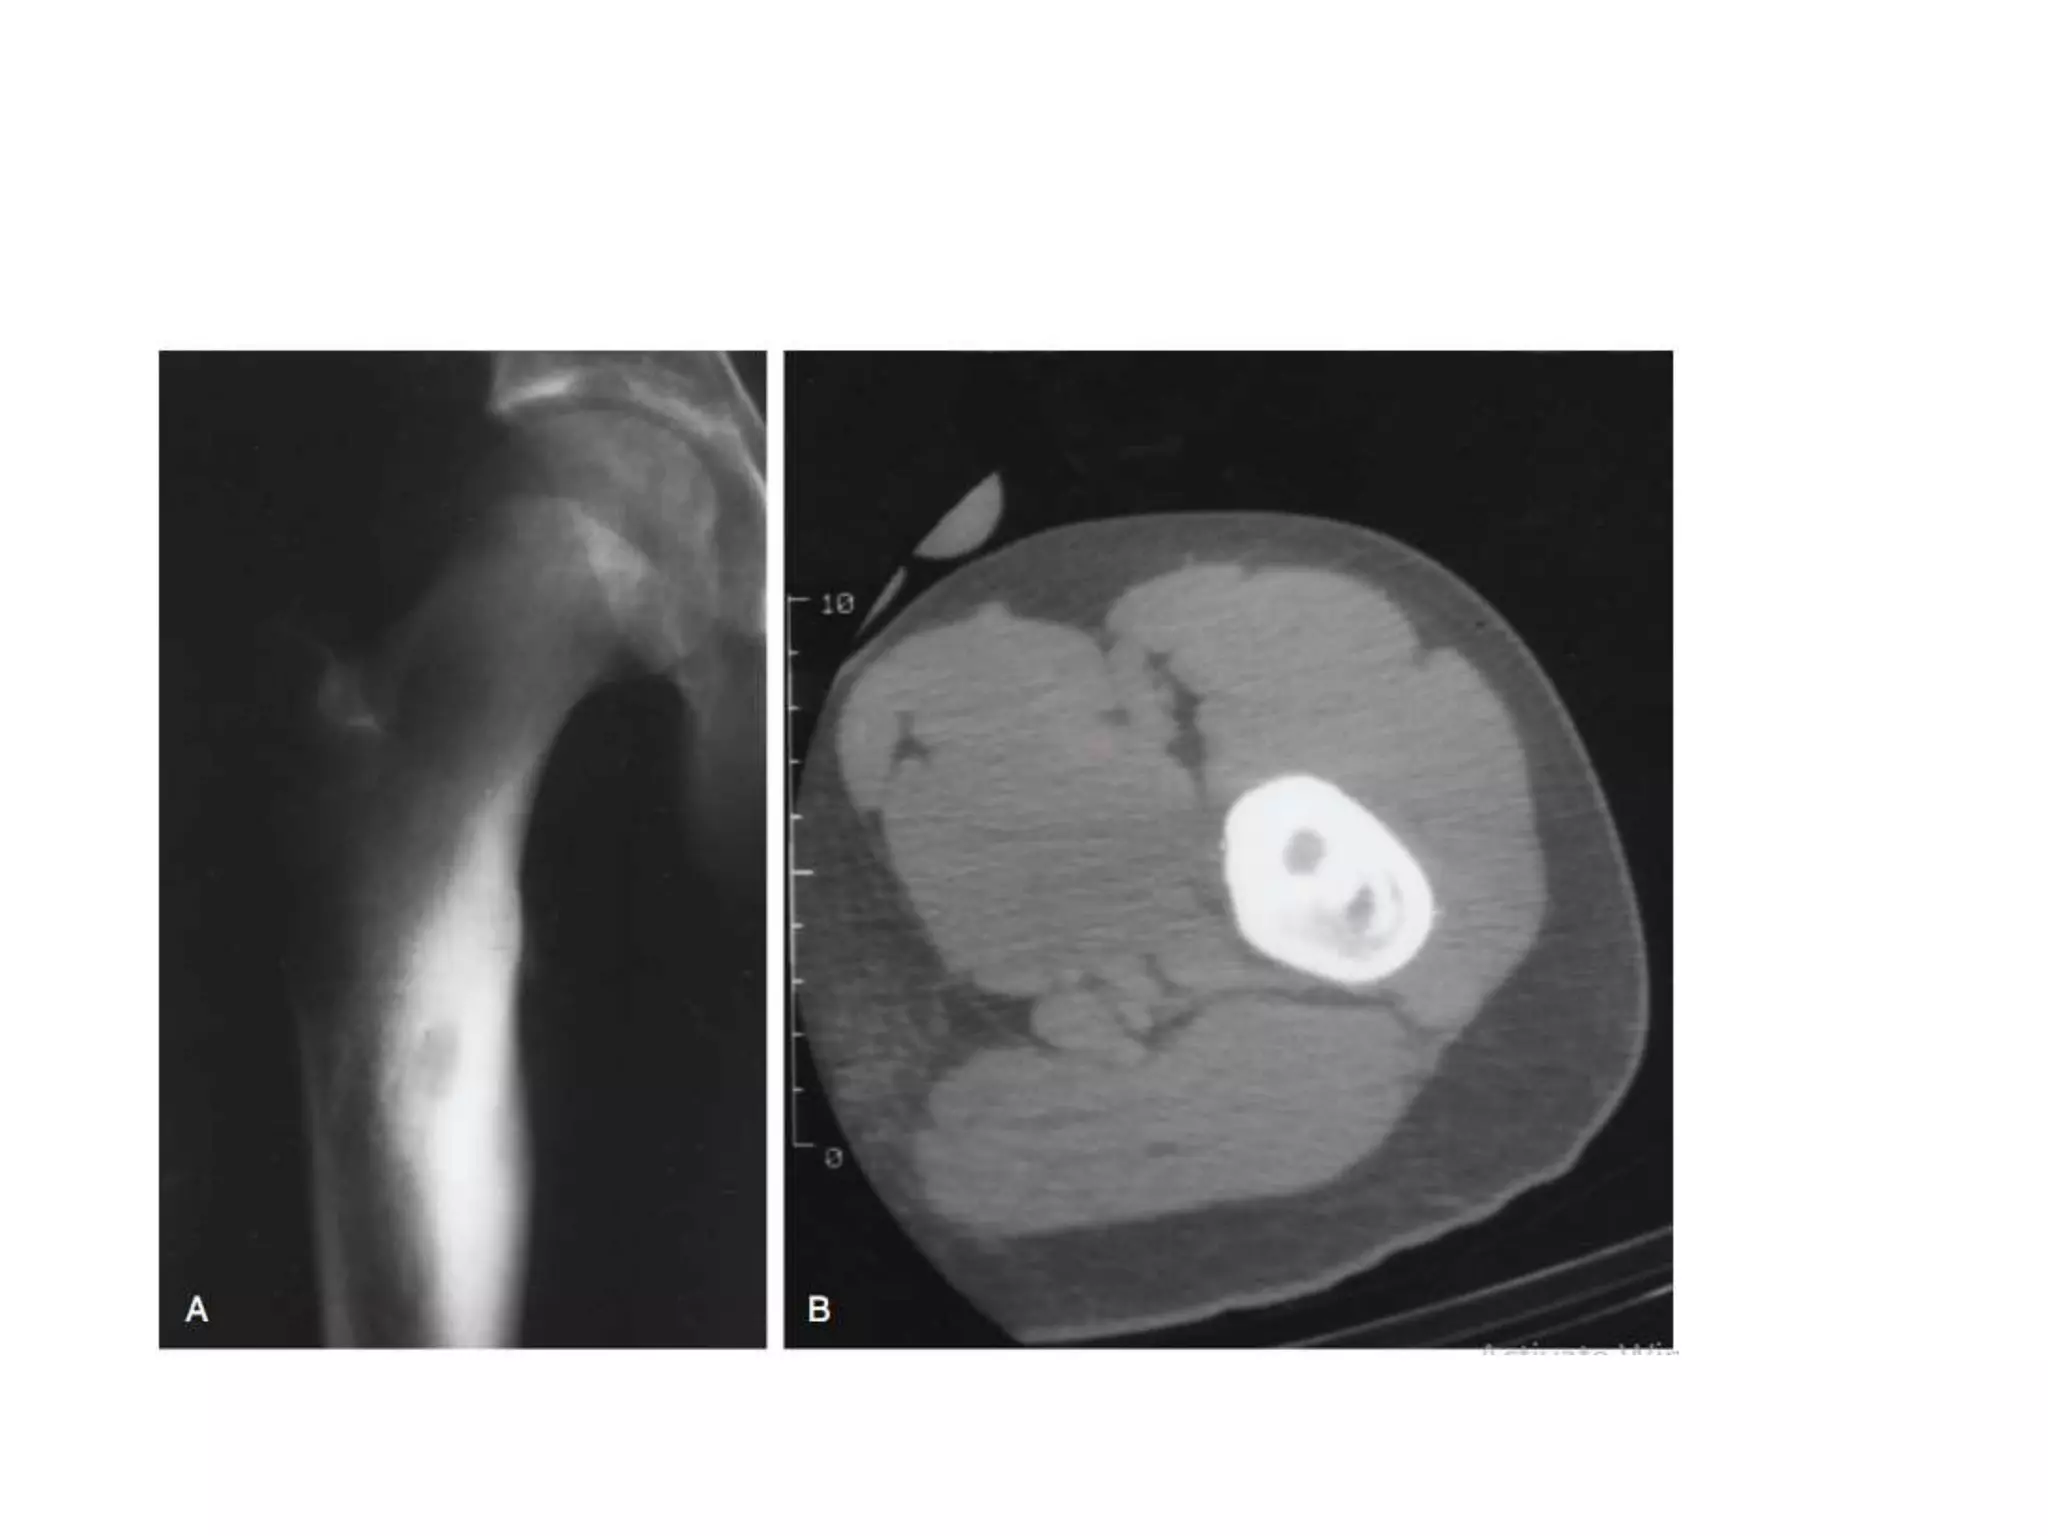

Osteoid osteoma

• Osteoid osteoma is a benign neoplasm most

often seen in young men 2nd and 3rd decade.

• M:F:: 3:1

• Pain is presenting symptom.

• Size less than 1.5cm

• Predilection for the lower extremity, with half

the cases involving the femur or tibia.

• X-ray : Small (<1.5 cm) central radiolucent nidus

with surrounding bony sclerosis. CT is best for

locating nidus.

• Microscopy : Fibrovascular tissue with immature

bony trabeculae that are rimmed by prominent

osteoblasts.

• Treatment :

Medical

Surgical

Percutaneous Radiofrequency ablation